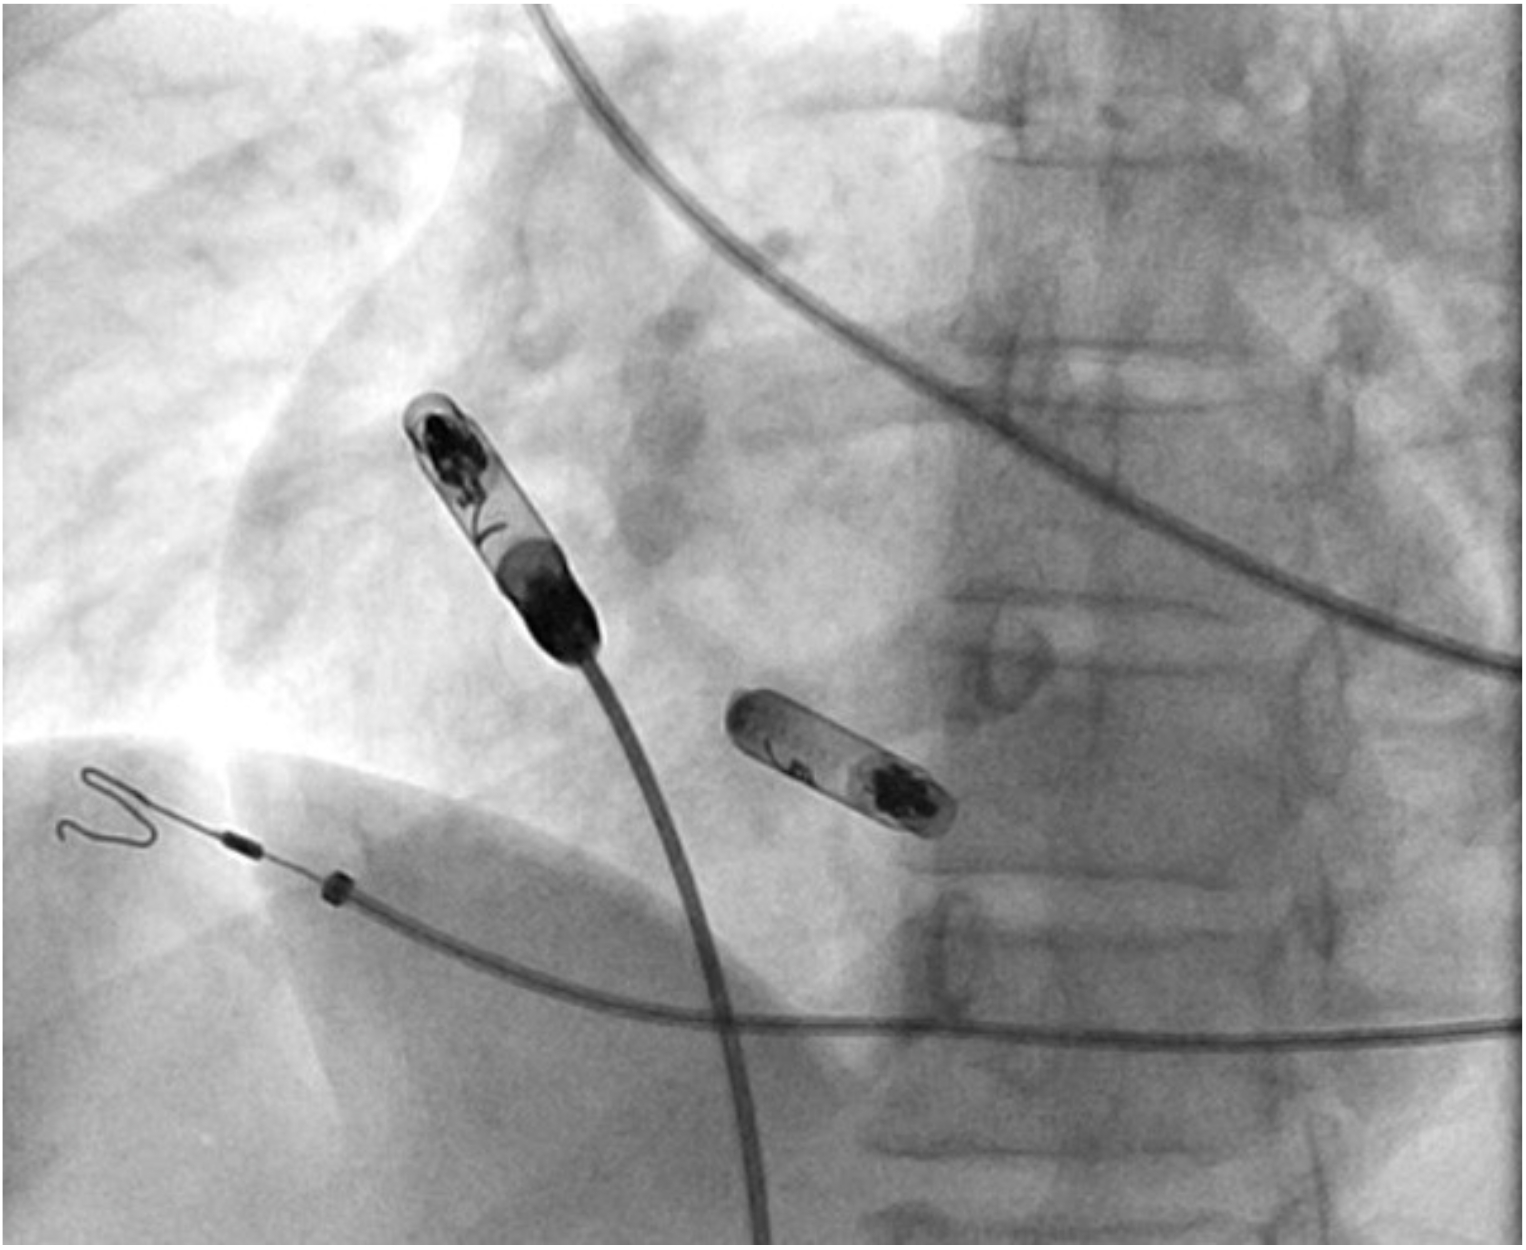

Case 1: 41-year-old female with symptomatic bradycardia, syncope and complete heart block underwent a dual chamber leadless pacemaker implantation. Electrical Mapping and current of injury was excellent. The device was implanted per protocol with one and half clockwise rotation. On postoperative day one, atrial loss of capture was noted. Chest X ray showed exaggerated device motion and revision was recommended. The pacemaker was removed using snaring and a new atrial leadless pacemaker was implanted. Upon reviewing the images from the first procedure, it was noticed that the chevron marker had rotated back (anticlockwise) around its axis leading to 'unscrewing' of the device.

Case 2: 84-year-old male with a history of atrial flutter ablation, type 2 Diabetes, and hypothyroidism presented with symptomatic bradycardia and sinus pauses. Patient underwent atrial leadless pacemaker implantation. Electrical Mapping and current of injury was excellent. Next morning, atrial loss of capture was noted. An abdominal x-ray revealed that the device had dislodged into the pelvis. Interventional radiology was consulted who retrieved the device via snare. Upon reviewing the images, we noted that post-implantation, the chevron sign had rotated anticlockwise half a rotation.

Our cases did not have any of the known risk factors for dislodgment. The anticlockwise movement of the chevron sign may serve as an early indicator of dislodgment. Particular attention should be paid to the movement of the chevron post-procedure. Other associations such as hypertrophic myocardium, genetics, and valvular and rhythm abnormalities could play a role in unscrewing the pacemaker and need to be closely studied.